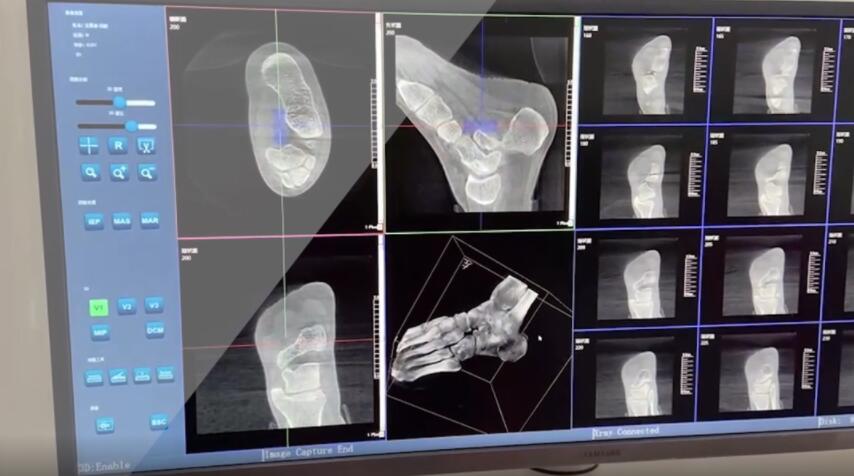

在術(shù)前,我們需要做三維掃描的CT檢查,我們必須要有CT的片子,還要有三維的重建。

在術(shù)中,我們怎么去判斷關(guān)節(jié)面平不平整呢?常規(guī)的正側(cè)位影像是不能判斷的。有些醫(yī)生為了準(zhǔn)確的判斷,可能會選擇做開放性的手術(shù),把關(guān)節(jié)暴露出來,在眼睛的直視下判斷關(guān)節(jié)面平不平整。但是關(guān)節(jié)全部打開,無疑增加了病人的創(chuàng)傷,而且增加了患者的恢復(fù)時間。所以如果在術(shù)中我們有三維影像的支持,對醫(yī)生做手術(shù)而言就會事半功倍,而且能夠大大的增加手術(shù)準(zhǔn)確度,增加患者術(shù)后的預(yù)后。所以在術(shù)中有三維影像的支持是非常必要的!

三維影像 看透關(guān)節(jié)內(nèi)骨折的“眼睛”